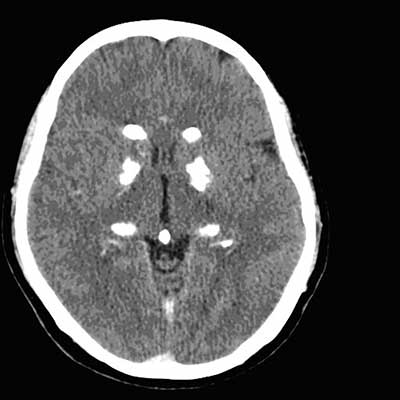

Huntington’s disease

atrophy of caudate head causes enlargement of frontal horns